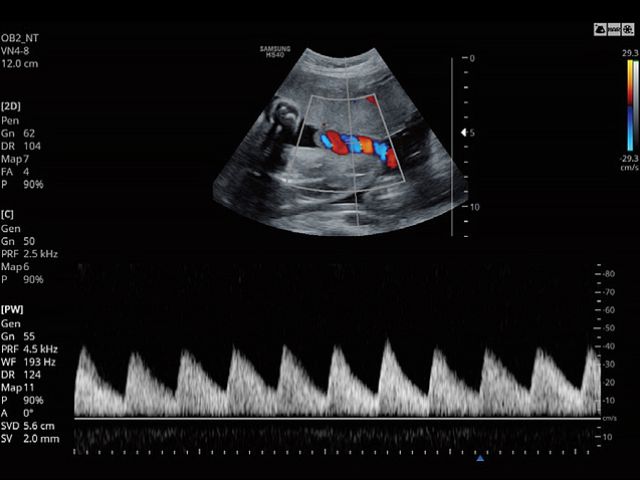

VN4-8Application:Abdomen, Obstetrics, Gynecology, Musculoskeletal, Pediatric, Vascular, Urology |